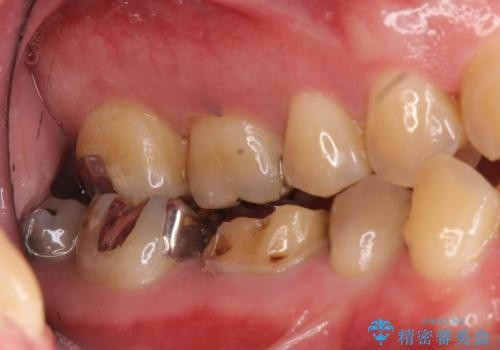

- 奥歯のかぶせものが取れたのと、手前の歯の虫歯治療を希望して来院。

奥歯は神経の治療からやり直し、セラミッククラウンとしました。

手前の歯は1本は虫歯、もう一本もつめものが取れたままでしたので、セラミックインレーとしました。

右下6番は、歯肉縁下カリエスではなかったため、そのまま補綴することが可能でした。